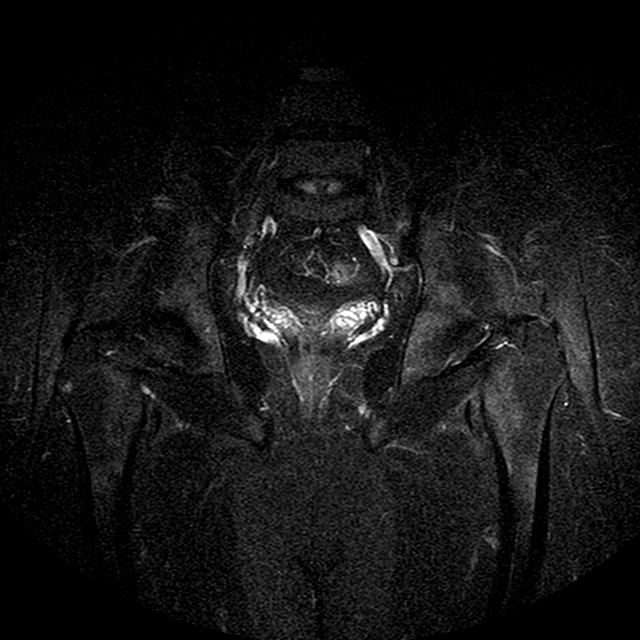

STIR

Evidenti e simmetriche alterazioni osteofitosiche in regione coxo femorale con riduzione delle rime articolari. Degenerazione completa del cercine glenoideo. Non attuali segni di versamento articolare. Non segni di edema osseo che escludono attuale algodistrofia od osteonecrosi. Lieve e simmetrica riduzione del trofismo della muscolatura glutea.